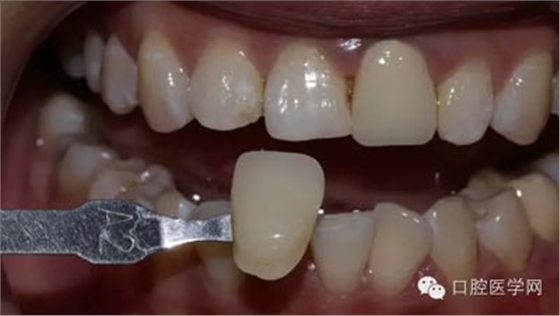

1、術(shù)前比色照

將比色照飽和度調(diào)到最低有助于牙齒明度的選擇